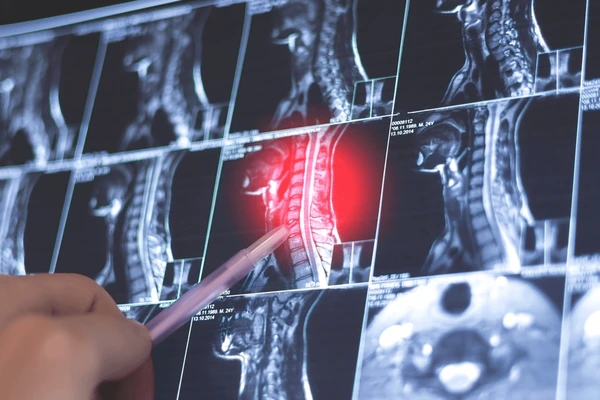

Chụp cộng hưởng từ (MRI) là một công cụ chẩn đoán mạnh mẽ được sử dụng để đánh giá các bệnh lý cột sống. Tuy nhiên, kết quả MRI đơn thuần không dùng để đưa ra chẩn đoán xác định. Sau khi bác sĩ khai thác kỹ tiền sử và thăm khám lâm sàng, MRI sẽ giúp xác nhận hoặc làm rõ hơn chẩn đoán nghi ngờ.

MRI trong lập kế hoạch phẫu thuật

MRI được sử dụng thường xuyên nhất để lập kế hoạch cho các ca phẫu thuật cột sống. Phim chụp này cung cấp hình ảnh chi tiết về các mô mềm, bao gồm đĩa đệm, dây thần kinh và tủy sống – những cấu trúc vốn không thể quan sát rõ trên X-quang hoặc chụp cắt lớp vi tính (CT scan).

Thông tin này đóng vai trò quyết định để xác định phương pháp tiếp cận ngoại khoa tốt nhất. Ví dụ:

- Nếu một khối thoát vị đĩa đệm đang chèn ép rễ thần kinh, MRI giúp phẫu thuật viên quyết định nên thực hiện lấy nhân đệm vi phẫu hay phẫu thuật nội soi.

- Trong các trường hợp hẹp ống sống nặng, MRI chỉ ra vị trí chính xác và mức độ hẹp, giúp phẫu thuật viên lập kế hoạch mở cung sống hoặc các quy trình giải ép khác.

Luôn tham vấn với chuyên gia về cột sống để xác định kết quả MRI được diễn giải trong mối tương quan với các triệu chứng, tiền sử bệnh và kết quả thăm khám lâm sàng từ đó có thể định hướng phương pháp điều trị tốt nhất phù hợp với tình trạng cụ thể của Anh/Chị.